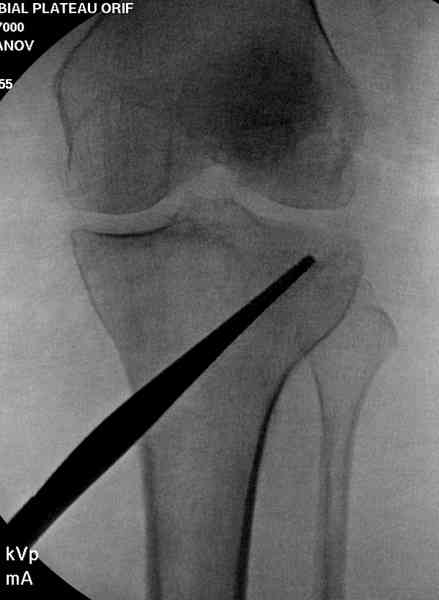

Из медиального окна можно приподнять латеральную

импрессию. Фиксация тремя параллельными шурупами в

эпифизарной части над импрессией. Создается крыша,

которая предупредит коллапс. На образовавшуюся полость - костная пластика из аутокости или синтетический заменитель. Мы применяем Osteoset в 4-5 мм диаметре таблеточки или иньекционную форму Prodens.